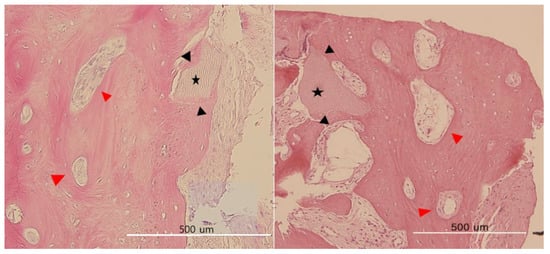

Histological Observations